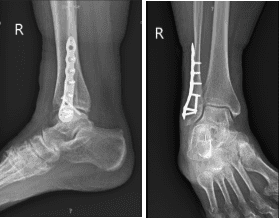

Radiografía Tobillo derecho mínimo 3 vistas

La fractura estaba bien reducida. La placa fibular distal se fijaba a la fíbula mediante una combinación de tornillos de bloqueo y no bloqueo. La imagen final fue tomada mediante fluoroscopia rotacional y se encontró en una posición aceptable. La herida fue irrigada y drenada.

El paciente fue atendido para revisión postoperatoria tras tres semanas, con resultados de radiografía que mostraron la fractura distal de la fíbula en curación tras el ORIF, sin evidencia de complicaciones físicas. Se recomienda comparar con radiografías postraumáticas/postoperatorias previas.